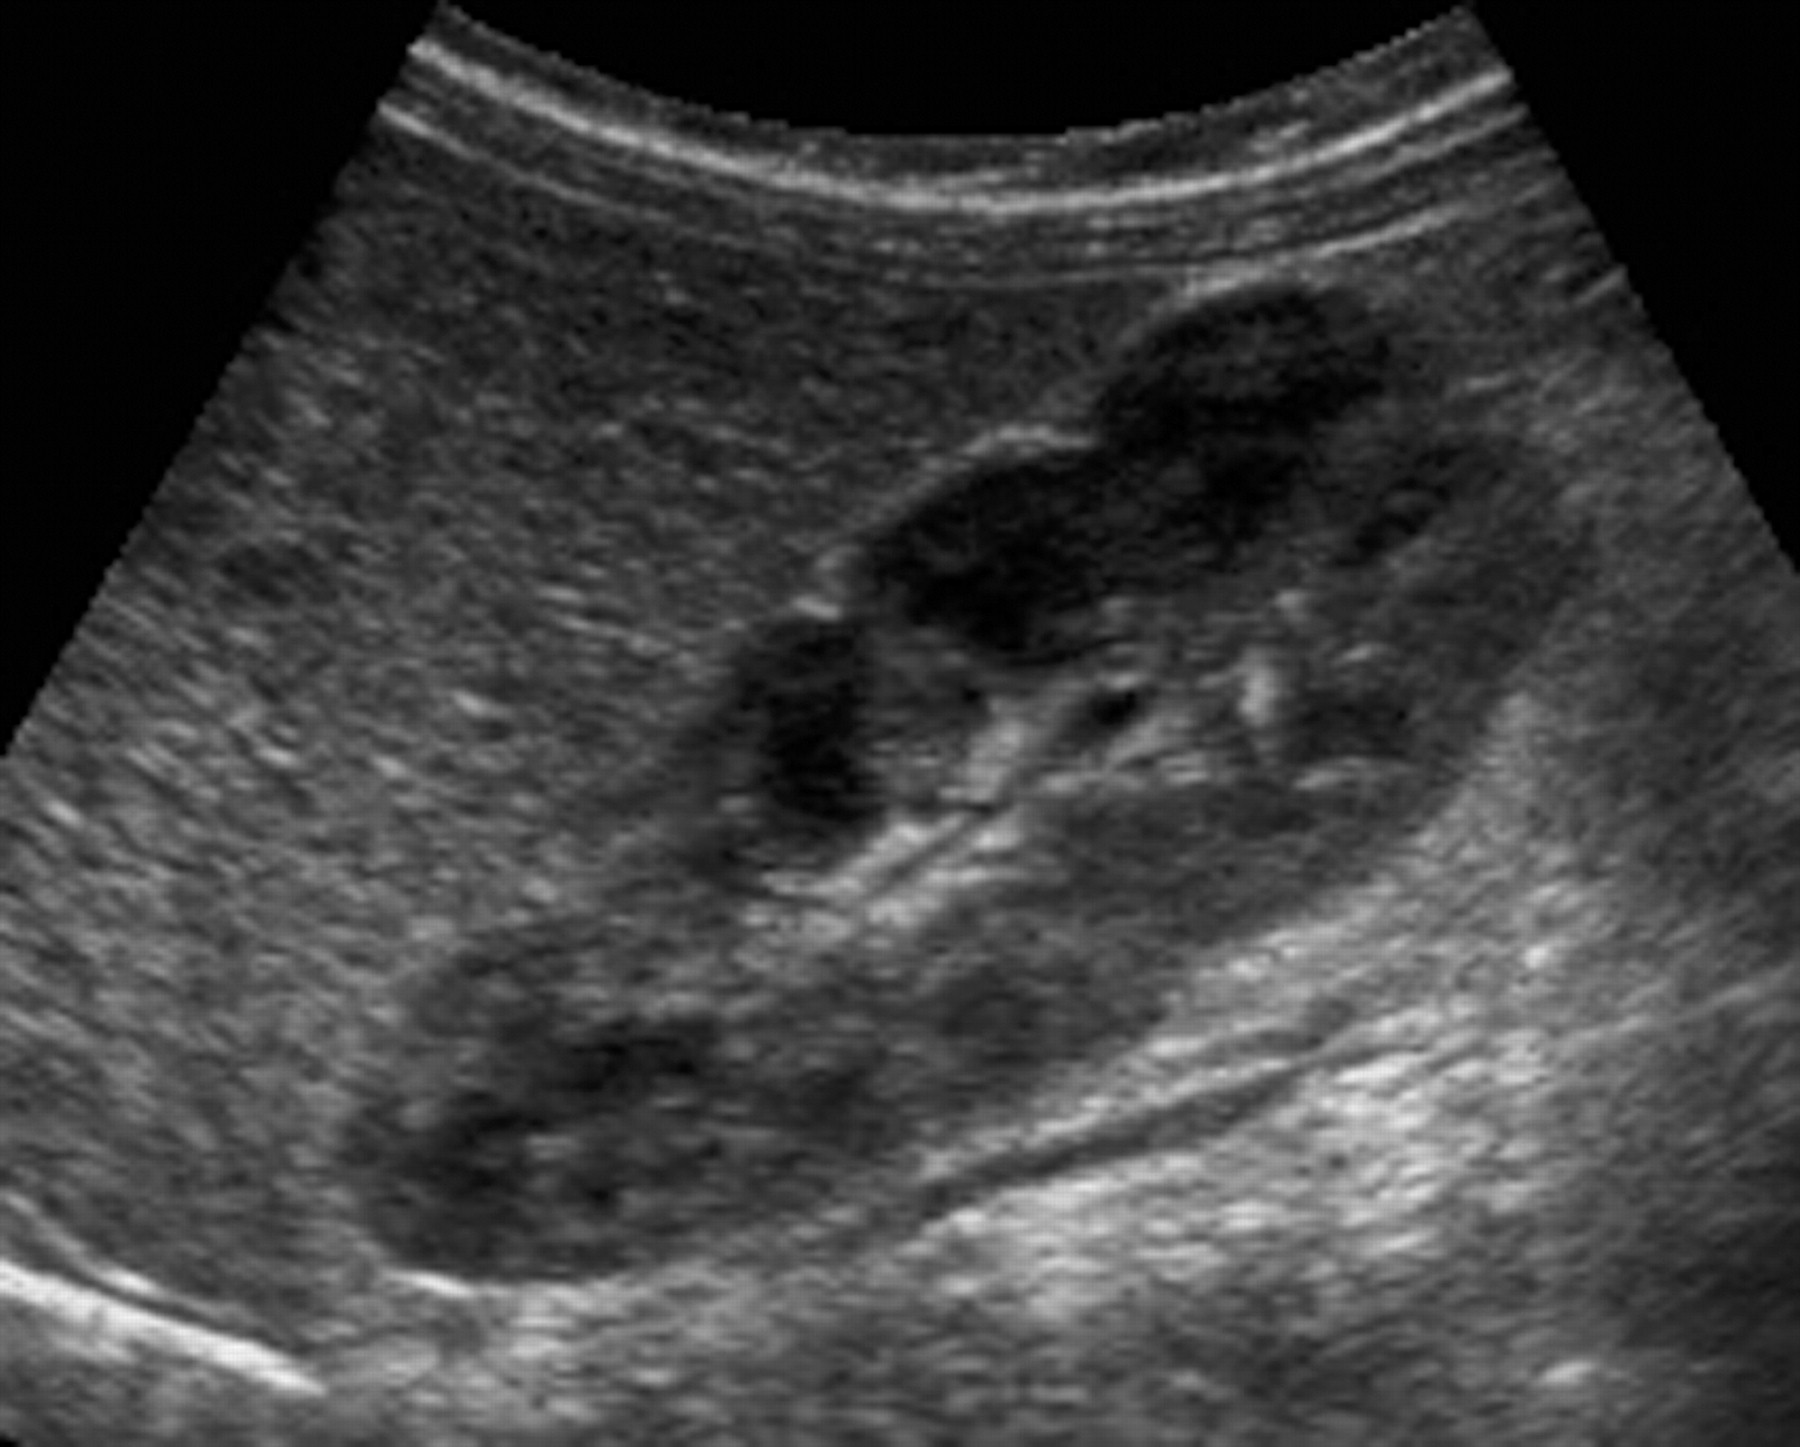

3-Duplex kidney

هذا مصطلح واسع يشمل عدة متغيرات منها وجود كليتين ملتصقات ببعض أو وجود two collecting systems في كلية واحدة. وهذه أيضا يوجد بها متغيرات أخرى من ناحية وجود حالب واحد أو حالبين ووجود شريان واحد أو اثنين.

يوجد هذا المتغير في قرابة ١٠٪ من الناس الطبيعيين. ويجب على الأخصائي التأكد من عدم توسع الحالبين وأيضا عدم وجود انسداد في أحد collecting systems وتحديدا العلوي.